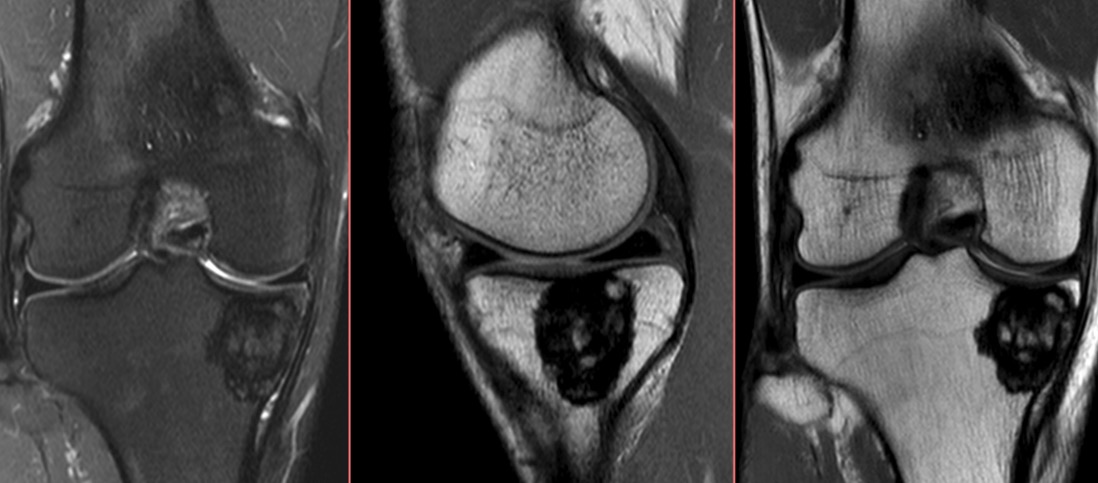

21 year old male with knee pain

Medial tibial plateau GCT. Loculated, intermediate T1, high T2 lesion with fluid level and thin sclerotic rim. Figure C = 3 year followup after curretage.

Giant cell tumor ( RID4309 )